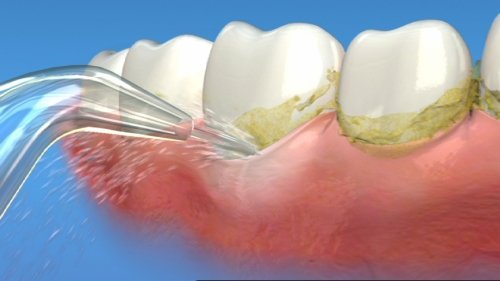

На фотографии представлен прибор ирригатор с различными насадками:

Принцип работы ирригатора: